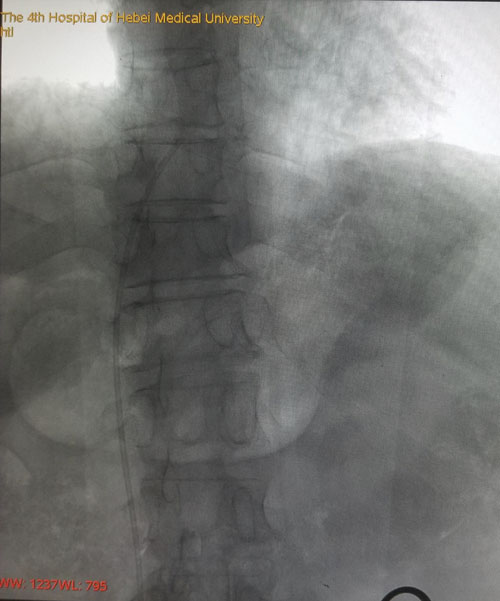

術后DSA評估導管尖端位置

本例患者由于是雙側乳腺癌術后伴雙側頸部及左胸壁廣泛轉移而來我院就診,難以建立常規輸液通路。乳腺中心回天立主管醫生通過查閱大量文獻資料并結合既往手術經驗,與宋振川主任反復商討后制定了股靜脈港的置入方案。手術當日,在超聲科紀曉惠主任、放射科楊光主任的協助下,成功將導管送達下腔靜脈與右心房結合部,港座埋置于右下腹壁皮下,完成了我省首例股靜脈穿刺靜脈港置入術。術后第一天患者恢復順利,下床活動良好,靜脈通路順暢。